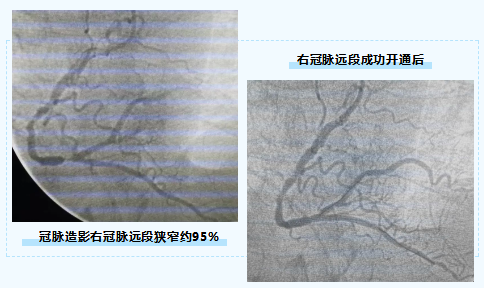

整个手术过程顺利,患者右冠脉远段狭窄约95%,急诊置入1枚支架开通血管后,病人胸痛消失,血压升至112/78mmHg,病人转危为安。